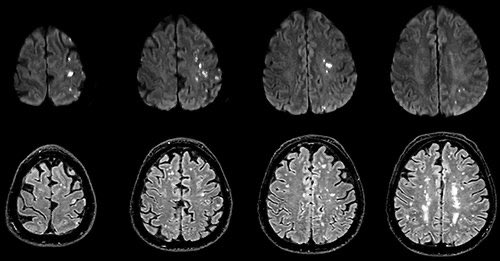

🔍ظهور السكتة الدماغية مباشرة بعد حقن الفلاكا🧠💉.

📖| المصدر:

#ref3" target="_blank" rel="noopener" onclick="event.stopPropagation()">karger.com